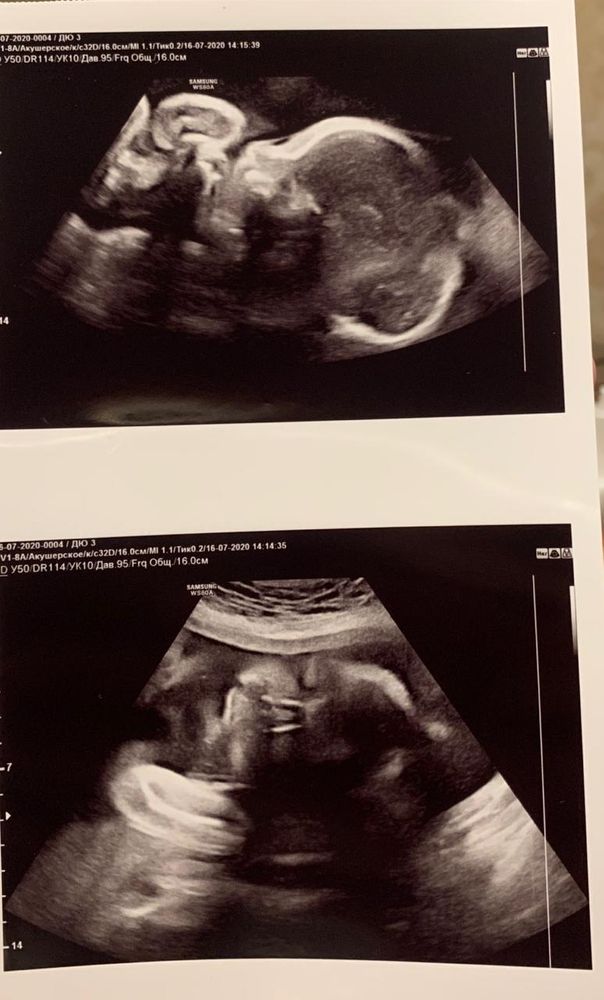

Моя многоплодная беременность от планирования до 36 недель